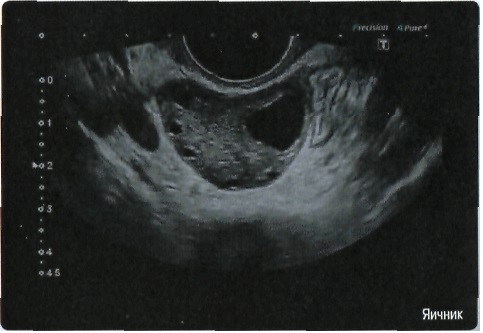

Гинекология:

Да

• Прецизионная визуализация (Precision Imaging) для послойного дифференцирования тканевых структур и высокой детализации;